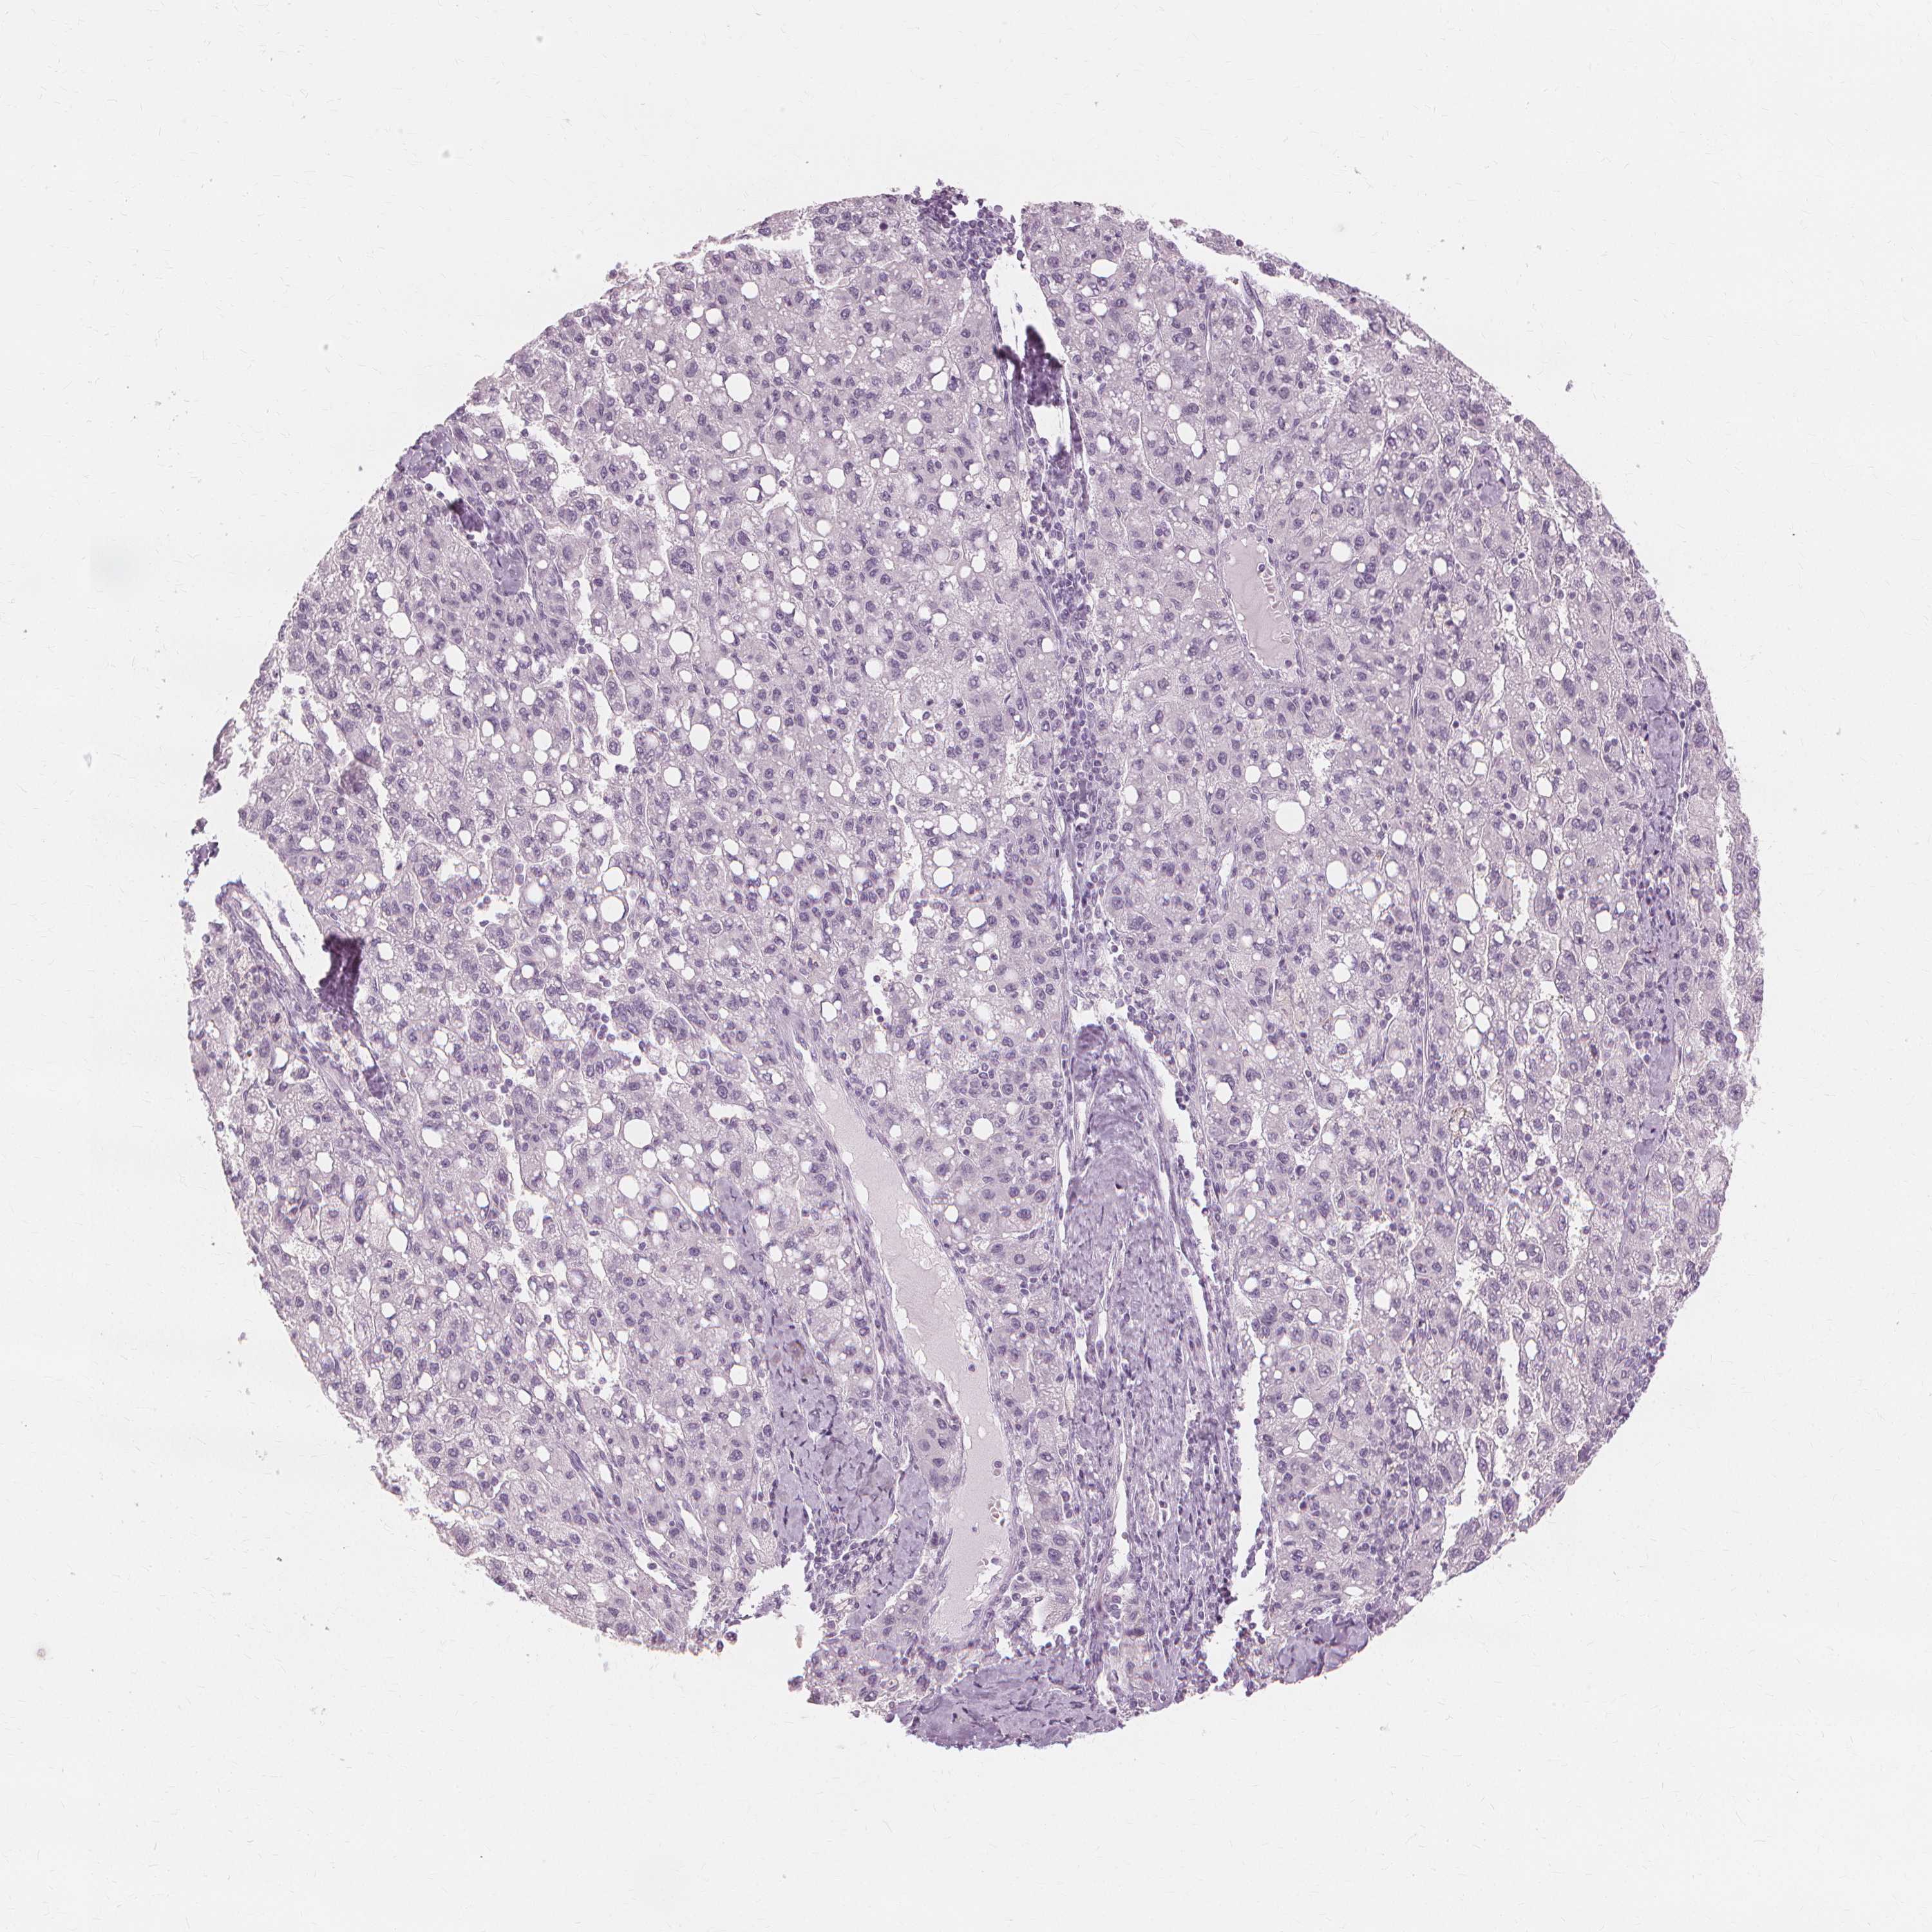

LIVER CANCER - Protein expressioni

A mouse-over function shows sample information and annotation data. Click on an image to view it in a full screen mode. Samples can be filtered based on level of antibody staining by selecting one or several of the following categories: high, medium, low and not detected. The assay and annotation is described here.

Note that samples used for immunohistochemistry by the Human Protein Atlas do not correspond to samples in the TCGA dataset.

Antibody stainingi

Antibody staining in the annotated cell types in the current human tissue is reported as not detected, low, medium, or high, based on conventional immunohistochemistry profiling in selected tissues. This score is based on the combination of the staining intensity and fraction of stained cells.

Each image is clickable and will lead to virtual microscopy that enables deeper exploration of all samples and also displays staining intensity scores, fraction scores and subcellular localization as well as patient and tissue information for each sample.

Antibody HPA023835

Staining

High

Medium

Low

Not detected

Intensity

Strong

Moderate

Weak

Negative

Quantity

>75%

75%-25%

<25%

None

Location

Nuclear

Cytoplasmic/membranous

Cytoplasmic/membranous,nuclear

Carcinoma, Hepatocellular, NOS

Cholangiocarcinoma